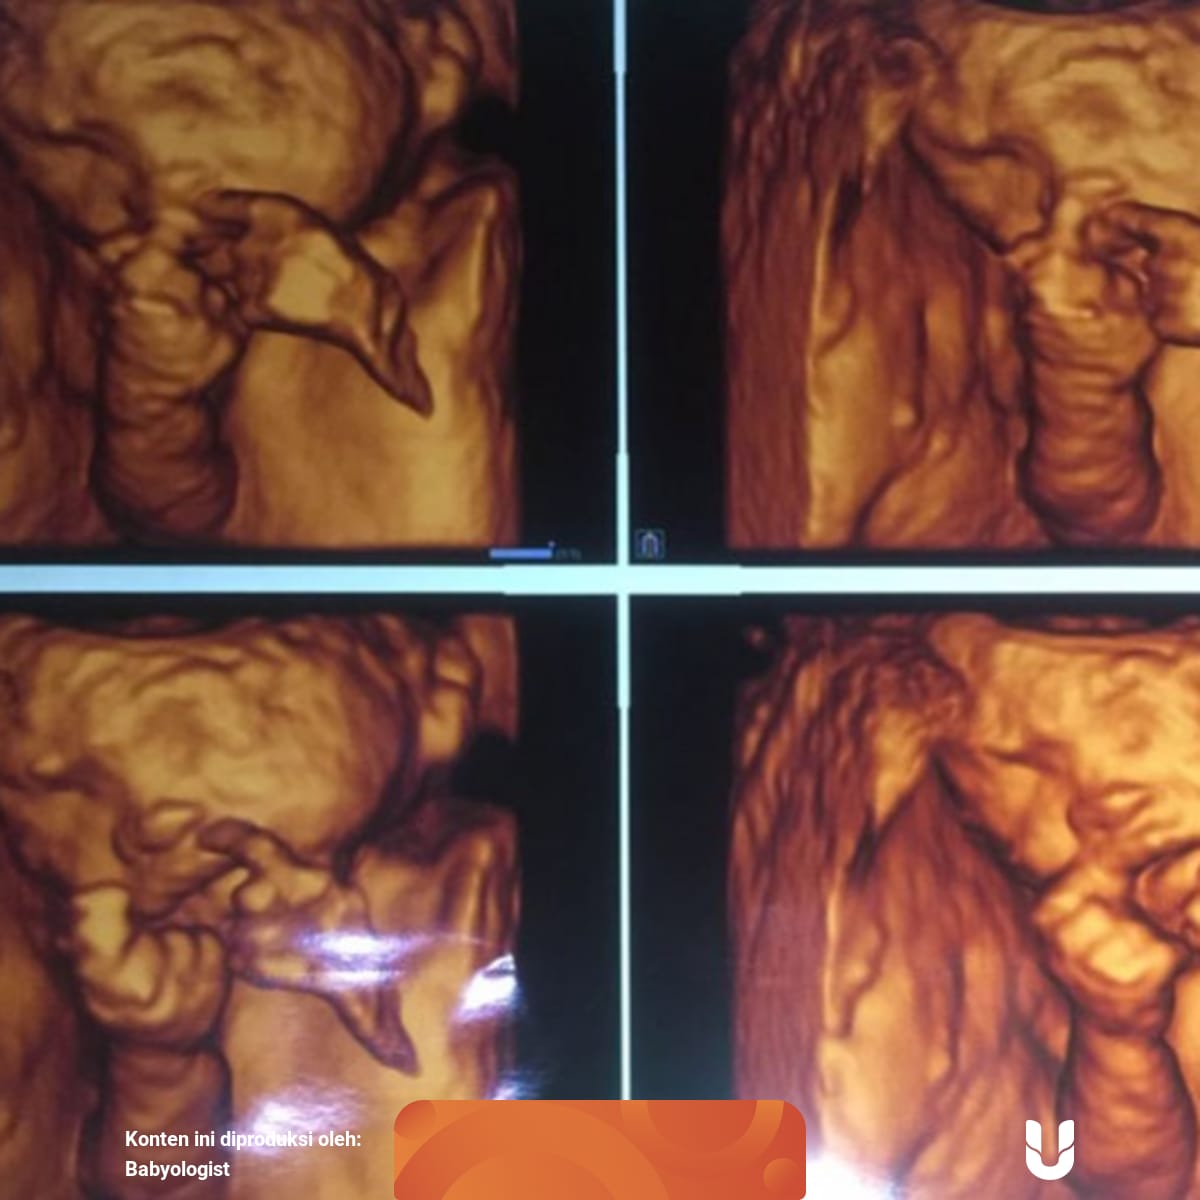

Kenali Cara Membaca Hasil USG Untuk Tahu Kondisi Bayi - Ibupedia

Kenali Cara Membaca Hasil USG Untuk Tahu Kondisi Bayi - Ibupedia